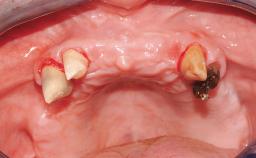

Immediate Loading of Six Implants in the Mandible and Six Implants in the Maxilla and Final Restoration with Full-Arch CAD/CAM Metal Framework FDPs Involving Digital Planning and Guided Surgery

Ali Tahmaseb, Renaat De Clerck, Daniel Wismeijer

Immediate loading of dental implants is increasingly popular with clinicians and patients. The idea of delivering a restoration directly after implant insertion,combined with a less invasive procedure (flapless protocol), has made treatment protocols involving dental implants more accessible to dentists and patients. However,immediate-loading concepts require sophisticated and exact planning. To facilitate this, conventional panoramic tomographs and periapical radiographs are often taken with the patient wearing a radiographic template simulating the preoperative prosthetic design. However, these radiographs do not provide all the necessary information. In addition, some protocols call for conventional surgical templates fabricated on the diagnostic cast. These will inform the bone drilling points and drill angles, but do not reference the underlying anatomical structures or provide exact 3-D guidance.